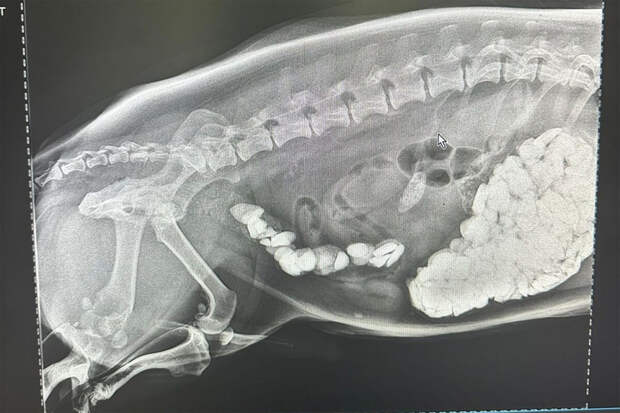

Собаку привезли в ветеринарную клинику - на рентгене врачи увидели большое количество камней в желудочно-кишечном тракте животного. После этого корги сделали срочную операцию - щебень необходимо было быстро извлекать.

Оперативное вмешательство прошло успешно - ветврачи достали из собаки 730 граммов щебня. Корги после операции заметно похудел, но стал выглядеть лучше, отметил источник. Ему назначили диету, сейчас животное восстанавливается.